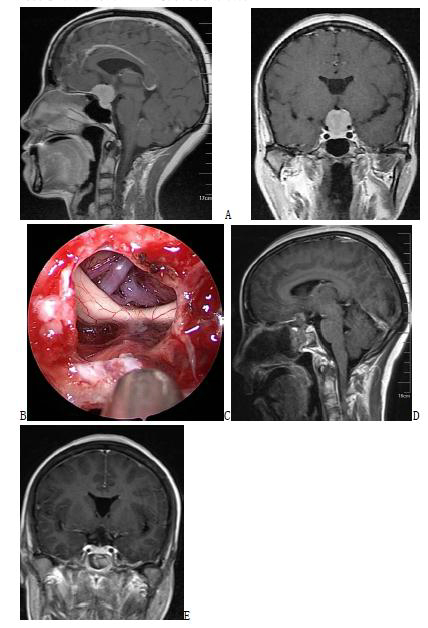

Figure 2. Enhanced MRI before surgery in A and B suggests recurrent giant full-slope chordoma; enhanced MRI after endoscopic transnasal surgery in C and D suggests complete tumor resection.

Figure 3. A and B Enhanced MRI before surgery suggest suprasellar craniopharyngioma; C Intraoperative screenshot suggests complete resection of the tumor, which can be seen in the three ventricles and the superior port of the midbrain aqueduct; D and E Enhanced MRI after endoscopic transnasal surgery, suggesting complete resection of the tumor.